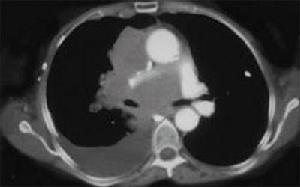

3.MRI表現:

①心包囊腫通常位於右心膈角區少數見於左心膈角區或其他部位。

②病變呈圓形或卵圓形邊緣光滑。

③漿液性心包囊腫呈長T1低信號和長T2高信號但當囊內蛋白含量高時則為短T1高信號,心膈角處特別是右側心膈角區單房性水樣密度腫塊邊緣光滑可確診為心包囊腫。